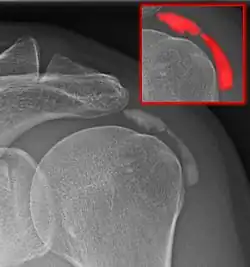

Arthrotische Veränderungen des Gelenkes, vor allem des Schultereckgelenkes (Akromioklavikulargelenk) haben Osteophyten zur Folge, die in den Raum, in dem der Oberarmkopf bzw. die Rotatorenmanschette bewegt wird, hakenförmig hineinwachsen können („Hook“). Auch hier ist eine schmerzhafte Bewegungseinschränkung die Folge.

Diagnostik

Aus dem klinischen Befund mit der zuweilen erheblichen Bewegungseinschränkung lässt sich die Schultersteife problemlos feststellen. Da damit aber noch keine Aussage über die Ursache dieser Symptomatik getroffen wurde, muss sich eine eingehendere Untersuchung anschließen. Dazu gehören grundlegend eine konventionelle Röntgendiagnostik und die Bestimmung geeigneter Laborparameter zur Erkennung entzündlicher Ursachen. Ergänzend können Ultraschall, Magnetresonanztomographie (MRT) und in seltenen Fällen auch Arthrographie[9] oder Arthroskopie sinnvoll sein.